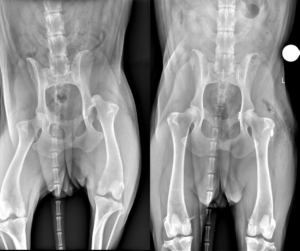

Fristoe raced to nearby Wellington Veterinary Hospital, where X-rays revealed Maisie Mae was leaking air into her chest and fluids into her abdomen. The vets stabilized her and called ahead to CSU’s James L. Voss Veterinary Teaching Hospital, where the emergency room staff was waiting for her.

Maisie Mae was alive, with a broken rib, and dislocated hip, but the blood loss and trauma to her lungs were life-threatening.

Her hip was popped back into place under sedation “but it re-luxated, so we took her to surgery and surgically stabilized the hip,” said Dr. Clara Goh, the CSU orthopedic surgeon who performed a toggle procedure on Maisie’s hip joint. “It’s essentially a prosthetic ligament to hold the joint in place, and she orthopedically recovered very well.”